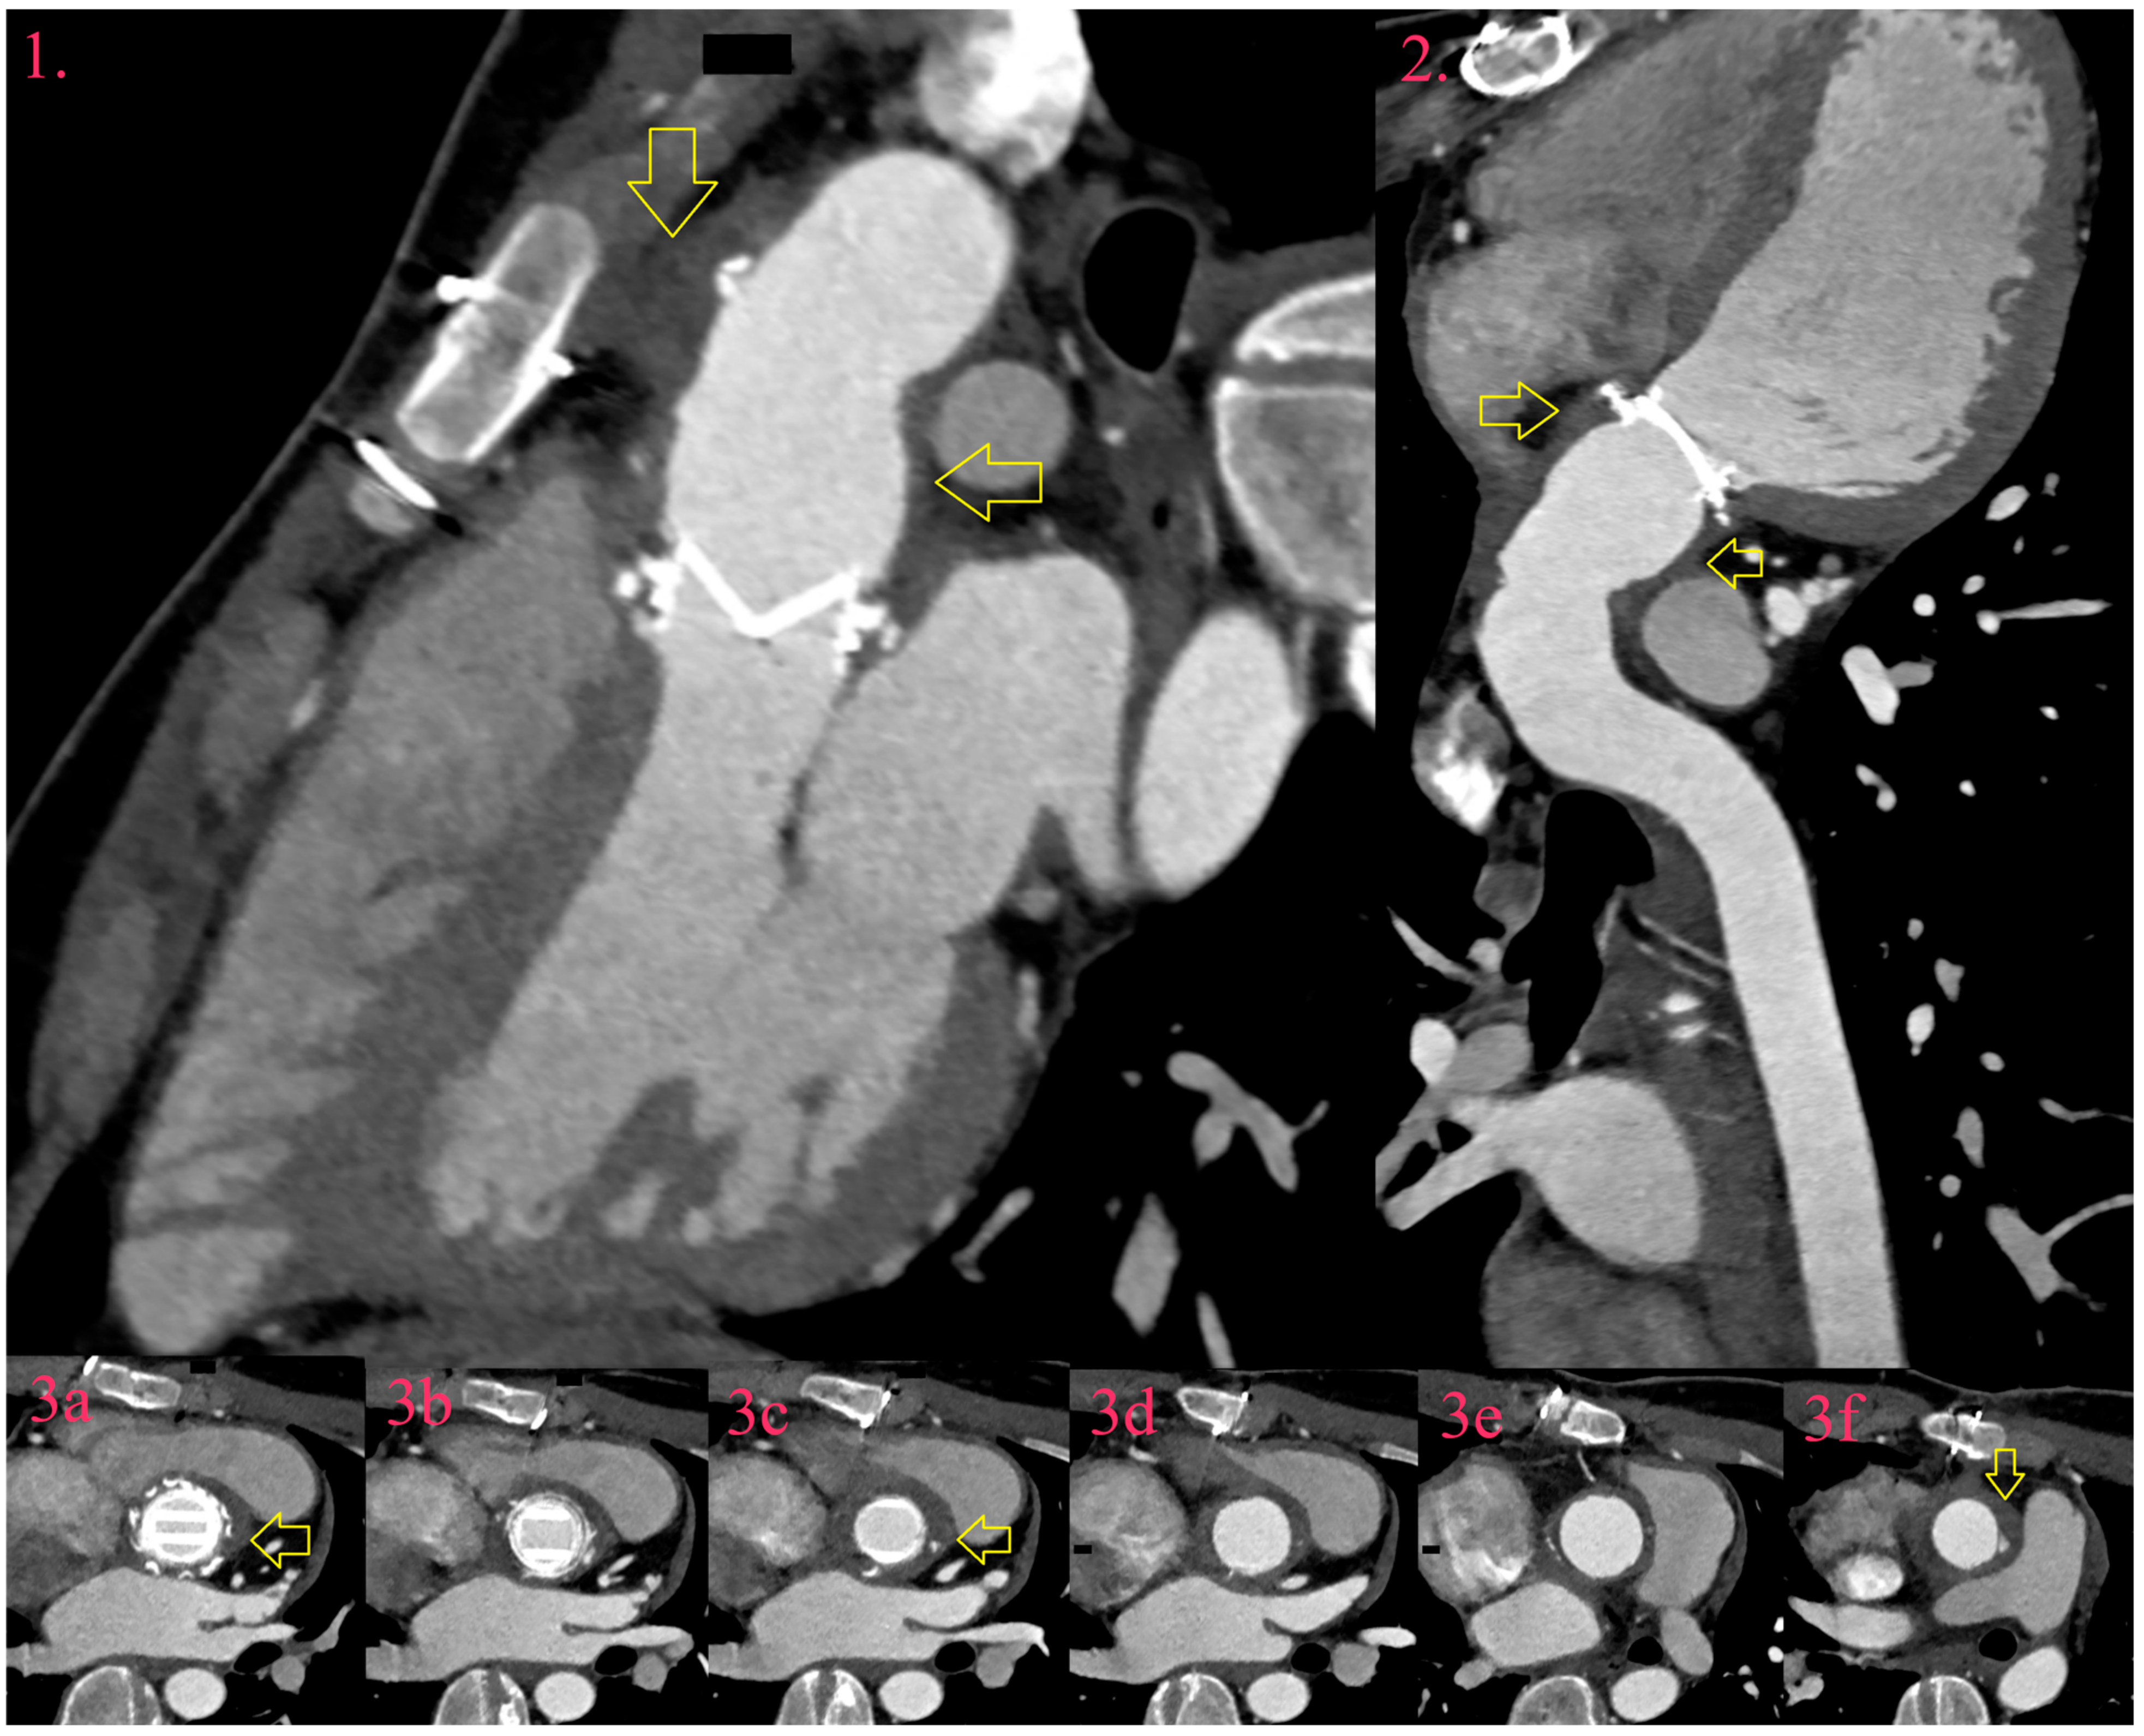

Figure 4.

IE of artificial aortic valve and graft after Bentall procedure. There is asymmetric hypodense thickening around valve and graft in three-chamber view (Image 1, yellow arrow), curved planar reformation (Image 2, yellow arrow), and trans-axial images (Image 3a–f, yellow arrow).

An abscess develops from cellulitis and is defined by the localization and degree of expansion outside the annulus, determining its thickness, width, and percentage of involvement of the annular circumference. In NVE, the infection most often spreads through the subcommissural zone, while in PVE, the infection spreads along the suture ring, often encompassing the entire circumference. In the paravalvular tissue, bacteria perform enzymatic degradation of connective and fatty tissue, sparing muscle tissue. The spread of the abscess around the aortic native valve depends on the site of infection entry. If the process begins to spread between the right and left coronary cusps, it will extend towards the right ventricle outflow (RVOT). If it starts between the right and non-coronary cusps, it will spread towards the membranous part of the interventricular septum and also towards the right atrium and Koch’s triangle, destroying the atrioventricular node and the upper end of the bundle of His. If it starts in the subcommissural zone of the non-coronary and left coronary cusps, it will spread towards the aortomitral fibrosis and the LVOT. In the case of abscess of the native mitral valve, if the process spreads from the anterior leaflet abscesses will develop into aortomitral fibrosis. If the abscess starts from the posterior leaflet, it will spread along the atrioventricular groove and may lead to separation of the left atrium from the left ventricle. In PVE, the abscess most often covers the entire circumference of the ring. However, in the case of an artificial aortic valve, larger abscesses are often located posteriorly and to the left, below the trunk of the pulmonary artery. Pathways of abscess spread are useful knowledge in reading CCT examination, as the density between the abscess and the surrounded epicardial fat is slightly brighter, which may lead to false negative findings [35].

CCT is superior in abscess detection regardless of valve type and location, in comparison to echocardiography. In particular, CCT is better in detecting abscesses around surgical materials, around patches and grafts. In reading potential abscess around the grafts, the reader should keep in mind that hypodense thin rim <3 mm is considered normal finding due to graft material, but only if it is not in contact with nearby soft tissue collection towards anterior mediastinum [31].